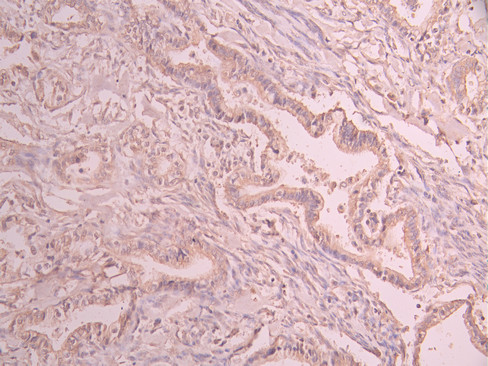

IHC image of CSB-RA044921A0HU diluted at 1:100 and staining in paraffin-embedded human cervical cancer performed on a Leica BondTM system. After dewaxing and hydration, antigen retrieval was mediated by high pressure in a citrate buffer (pH 6.0). Section was blocked with 10% normal goat serum 30min at RT. Then primary antibody (1% BSA) was incubated at 4°C overnight. The primary is detected by a Goat anti-rabbit polymer IgG labeled by HRP and visualized using 0.05% DAB.